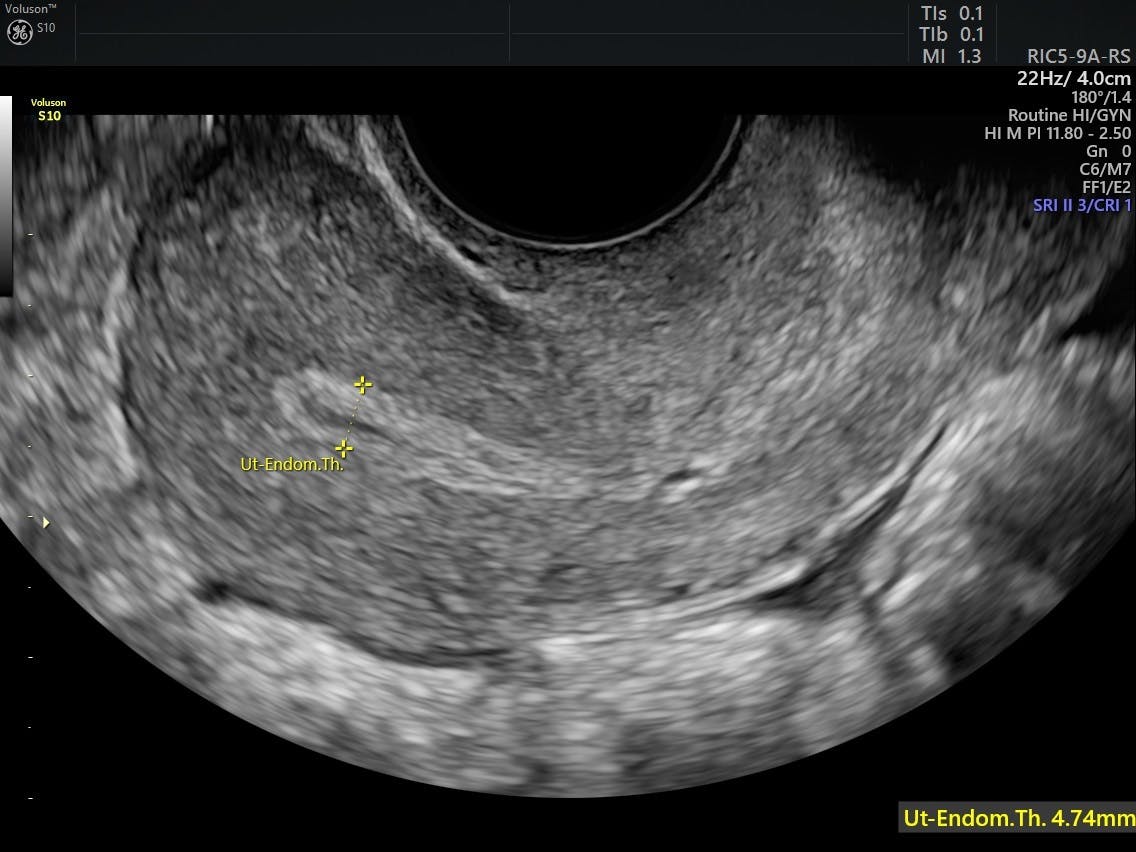

Brown Spotting After Menopause 9 Causes from i0.wp.com For most people who do bleed after menopause, it occurs within the first year, and chances become less and less the longer someone has been in menopause. The mean endometrial thickness in postmenopausal women is much thinner than in most women with pmb will not have significant pathology but the dictum remains that postmenopausal bleeding is cancer until proved otherwise. Endometrial polyps, very thin endometrial or vaginal lining (atrophy) because of low oestrogen levels. It should always be followed up, as it may be a sign of cancer. In retrospect i did have a sore left hip and years of severe constipation. Typically, postmenopausal women who experience bleeding are referred for further testing to either rule out or diagnose endometrial cancer. Endometrial cancer is the most. Post menopausal bleeding refers to any vaginal bleeding after the menopause.

Once women have gone through the menopause, they should not experience any bleeding, spotting or coloured discharge. @article{adamson1957postmenopausalb, title={post‐menopausal bleeding *}, author={t. When periods have stopped for more than a year in women who are generally over 45 years, or in younger women whose ovaries have failed early. Postmenopausal bleeding always needs evaluation because sometimes it maybe concerous also. However, the condition can be extremely dangerous and would need to be checked by a qualified physician immediately to rule out harmful medical anomalies like endometrial cancer. Many women consider post menopausal bleeding (vaginal bleeding after menopause) to be normal. Endometrial polyps, very thin endometrial or vaginal lining (atrophy) because of low oestrogen levels. Post menopausal bleeding, endometrial thickness, transvaginal scan, endometrial post menopausal bleeding is defined as abnormal uterine bleeding occurring one year after cessation there is 10% risk of having endometrial cancer in post menopausal bleeding women whereas risk. It can be a symptom of vaginal dryness, polyps (noncancerous in about 10% of women, bleeding after menopause is a sign of uterine cancer. Menopausal hormone therapy once seemed the answer for many of the conditions women face as they age. This procedure is usually done if it is not possible to obtain a sample of cells when a pipelle is performed or if an ultrasound shows that the lining of the uterus is. Postmenopausal bleeding is not usually serious, but can be a sign of cancer. Vaginal bleeding after menopause may be a sign of a serious disorder.

The mean endometrial thickness in postmenopausal women is much thinner than in most women with pmb will not have significant pathology but the dictum remains that postmenopausal bleeding is cancer until proved otherwise. Stephanie describes post menopausal problems, specifically bleeding that could be a sign of uterine cancer. The primary symptom of endometrial cancer (eca) is postmenopausal bleeding (pmb). Once women have gone through the menopause, they should not experience any bleeding, spotting or coloured discharge. Postmenopausal bleeding is not usually serious, but can be a sign of cancer. Although bleeding after menopause is not always cause for concern, a woman should always consult her doctor if she does have postmenopausal bleeding to rule out more serious causes, such as endometrial cancer. @article{adamson1957postmenopausalb, title={post‐menopausal bleeding *}, author={t. Post menopausal bleeding, endometrial thickness, transvaginal scan, endometrial post menopausal bleeding is defined as abnormal uterine bleeding occurring one year after cessation there is 10% risk of having endometrial cancer in post menopausal bleeding women whereas risk. Post menopausal bleeding refers to any vaginal bleeding after the menopause. While vaginal bleeding has been known to be a symptom of endometrial cancer. This may lead to cancerous changes in the uterine lining. Typically, postmenopausal women who experience bleeding are referred for further testing to either rule out or diagnose endometrial cancer. Mary ann lumsden university of glasgow.

Menopausal hormone therapy once seemed the answer for many of the conditions women face as they age. Bleeding is the most common symptom of endometrial or uterine cancer after ultrasound and biopsy are usually done in your doctor's office. It should always be followed up, as it may be a sign of cancer. Pmb can be caused by vaginal, cervical, uterine or ovarian cancers. Typically, postmenopausal women who experience bleeding are referred for further testing to either rule out or diagnose endometrial cancer. Postmenopausal bleeding is vaginal bleeding that occurs a year or more after your last menstrual period. Postmenopausal bleeding is vaginal bleeding that happens at least 12 months after your periods have stopped. While vaginal bleeding has been known to be a symptom of endometrial cancer. However, the condition can be extremely dangerous and would need to be checked by a qualified physician immediately to rule out harmful medical anomalies like endometrial cancer. How your doctor will investigate postmenopausal bleeding. The mean endometrial thickness in postmenopausal women is much thinner than in most women with pmb will not have significant pathology but the dictum remains that postmenopausal bleeding is cancer until proved otherwise. If you've reached menopause, you probably thought that your days of any bleeding down there were over—but then you saw blood. Endometrial cancer is the most.